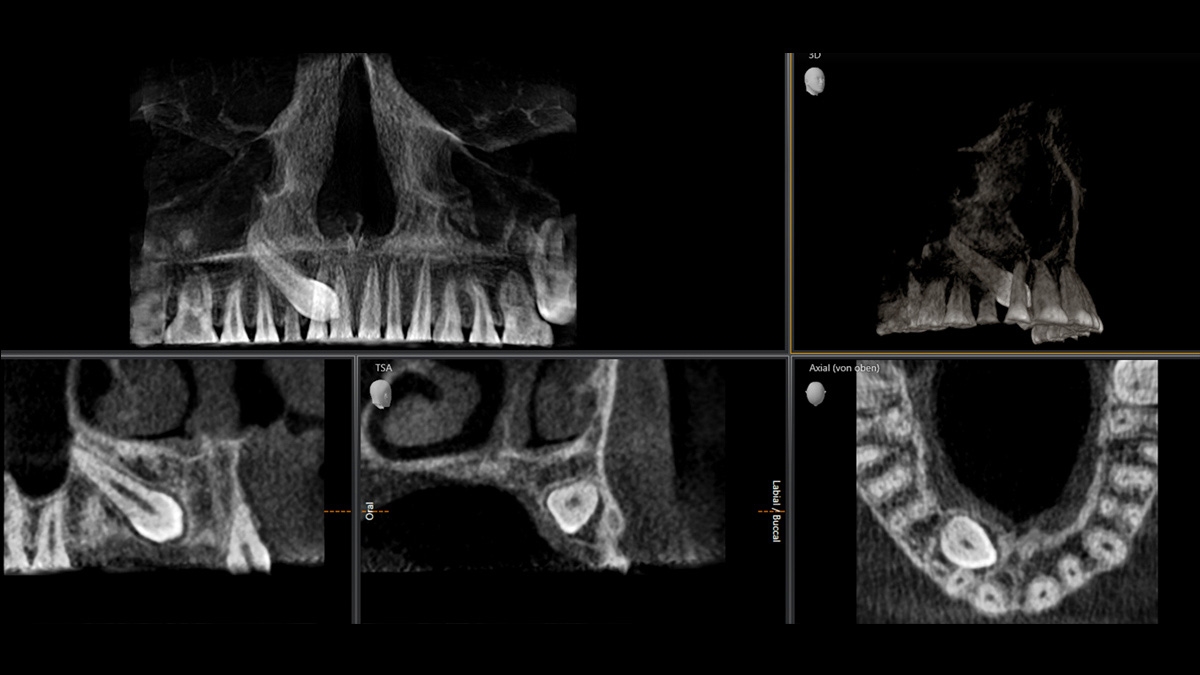

3D according to your needs

With the Low Dose and HD function, you can capture 3D images in the dose range of 2D X-ray and HD images with up to 80 μm resolution

Flexible volume

From ø 5 cm x 5.5 cm to ø 11 cm x 10 cm

Flexible volumes for a variety of indications

Coordinated volume sizes for your needs from Ø 5 x 5.5 cm to Ø 11 x 10 cm

3 different volumes